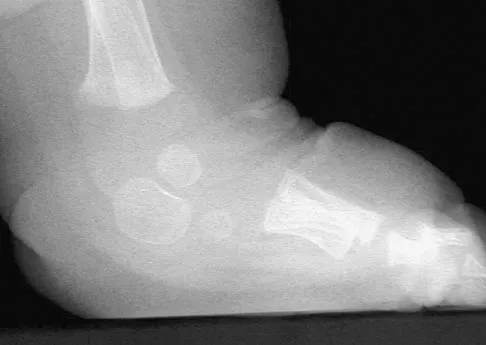

Figure 39 shows the radiograph of a 4-month old infant who has been undergoing weekly casting since birth for a congenital equinovarus deformity. Management should now consist of

Explanation

The radiograph shows the development of a rocker-bottom foot deformity. A rocker-bottom foot occurs in the treatment of clubfoot when casting is continued in the presence of a very tight gastrocnemius-soleus complex and an uncorrected hindfoot. While there are some preliminary reports on using Botox injection and continued casting for the equinus deformity, most authors recommend posterior or posterior medial release. Percutaneous tenotomy has been recently recommended with the resurgence of the Ponsetti technique. Lehman WB, Atar D: Complications in the management of talipes equinovarus, in Drennan JC (ed): The Child's Foot and Ankle. New York, NY, Raven Press, 1992, pp 135-136. Herring JA: Tachdjian's Pediatric Orthopedics, ed 4. Philadelphia, PA, WB Saunders, 2002, pp 927-935.